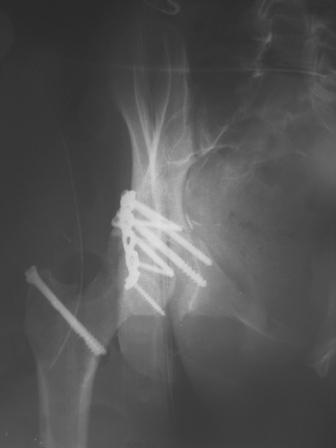

30/11/04 |  30/11/04 |  30/11/04 |  14/12/04 |  14/12/04 |  14/02/05 |  14/02/05 |  21/02/05 | Уважаемые коллеги! Случилось вторичное смещение вертлужной впадины после операции. Посоветуйте, что делать. Пациентка 18 лет. Травма 19.11.04. D.s.: Закрытыый Т-образный высокий перелом правой вертлужной впадины. Закрытый перелом м\мыщелкового возвышения левой б\берцовой кости. 9.12.04 операция - открытая репозиция, остеосинтез переломам вертлужной впадины. 30.12.05 выписаны на амбулаторное лечение с рекомендациями не вставать на правую ногу. 14.02.05 при контрольном осмотре на Р-граммах выявлено вторичное смещение передней колонны. Клинически подвывиха нет, имеется умеренная приводящая контрактура правого тазобедренного сустава, гипотрофия мышц н\конечностей. Госпитализирована в травмотделение. Выполнено КТ. Имеется смещение передней колонны кнутриЮ диастаз 8 мм. Посоветуйте пожалуйста, что предпринять в данной ситуации.

У больной имеется диастаз лонных и седалищных костей, то есть "разорвано" тазовое кольцо. В перспективе возможно образование ложного сустава на уровне основания лонной кости с болевым синдромом, поскольку седалищная кость не срастется.

1.сейчас провести пластику через подвздошный доступ для сращения лонной кости.

2. ограничить двигательную активность до 6 мес. (не нагружать ногу, носить тазовый корсет-пояс и т.д.) с контролем сращения. Вроде бы на Р-граммах угадывается слабая тень формирующегося костного мостика по l. iliopectinea, это место в представленные срезы КТ не попало. Если к 6 мес. ничего не нарастет, то см. пункт 1.

В любом случае начинать нагрузку на эту ногу до уверенности в сращении - большая вероятность исхода в псевдартроз с болевым синдромом.